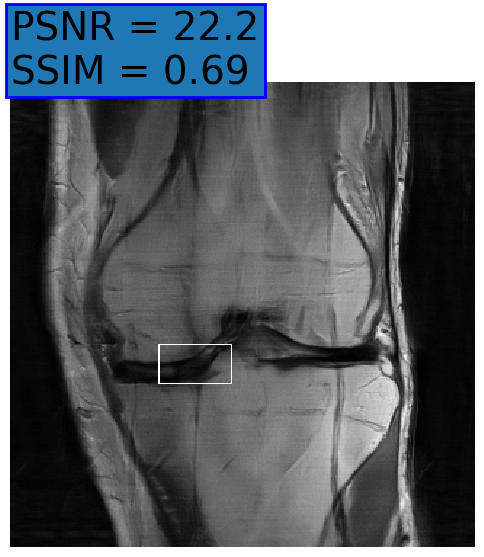

Figure 6: Examples of reconstruction results. Rows 1, 3, and 5: The reference (GT) fully sampled image, the reconstructed images obtained by the three models (1-3), NPB-REC, baseline, E2E-VarNet trained with Dropout, and the Std. map derived from our method for example from the knee dataset, the brain dataset, and the brain dataset sampled with radial mask L=50𝐿50L=50, respectively. Rows 2, 4, and 6: The corresponding annotated ROIs of the cartilage, edema, and nonspecific white matter lesion respectively.

Fig. 6 depicts the reconstruction results obtained by (1) our NPB-REC approach, (2) the baseline, and (3) Monte Carlo Dropout, for examples of both the knee (row 1) and the brain (rows 3 and 5) datasets. The first two examples were obtained by the models that trained on brain data and were tested on knee data (row 1) and vice versa (row 3). In knee images, all three models exhibit minimal differences in handling pronounced folding artifacts. However, our approach demonstrates superior reconstruction performance for anatomical annotations or pathological regions, labeled by radiologists, in terms of both PSNR and SSIM. The last example is a reconstructed brain image that was obtained by the three models, where the k-space input is undersampled by a radial mask with L=50𝐿50L=50. Table 2 presents the mean PSNR and SSIM metrics, calculated over the whole inference knee dataset, for the three models that were trained on brain data. The NPB-REC method shows a considerable improvement in the generalization ability on knee data for higher acceleration rates R=8𝑅8R=8 and R=12𝑅12R=12 in both annotation regions and the whole images. However, both the baseline and Dropout methods show a slight improvement in the metrics in the case of a small acceleration rate R=4𝑅4R=4. Table 3 shows the results of the inverse experiment, i.e. calculating the mean PSNR and SSIM metrics over the whole brain inference set for the three models that were trained on knee data only. The generalization capability of the three models in the case of an anatomical distribution shift from the knee to the brain is better than the opposite scenario. This is not only measured quantitatively by the SSIM and PSNR metrics, but also visible in the predicted reconstructions. For instance, the brain MRI reconstructed images exhibit fewer artifacts than the produced knee images, as shown in row 1 vs. row 3 in Fig. 6.

Table 3 presents the mean PSNR and SSIM metrics calculated over the whole inference knee dataset that were obtained by the three models, where the k-space input is undersampled by a radial mask with L=50𝐿50L=50 and L=40𝐿40L=40. Although the NPB-REC approach improves the accuracy of reconstruction when the metrics are measured on the whole image, it doesn’t yield the best performance on the annotation ROIs. However, it is still able to reconstruct high-quality images while preserving the important anatomical content in these annotations. This can be clearly observed in the last row in Fig. 6, where the topmost part of the ROI image predicted by NPB-REC is preserved, in contrast to the other benchmarks.